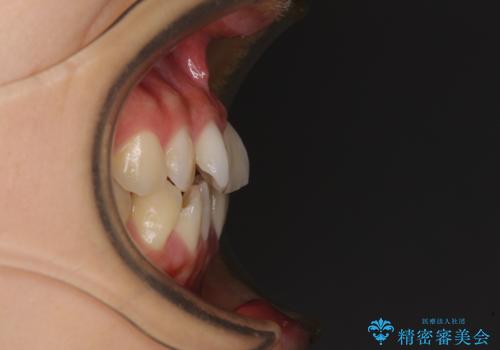

前歯のクロスバイト ワイヤー装置を併用したインビザライン矯正

- 前歯の捻転とクロスバイトが気になり、インビザラインによる矯正治療を希望して来院された患者様です。

上顎側切歯(上の真ん中から2番目の歯)が舌側転位している場合、インビザラインでは仕上げきれないことが多く、更には無理して動かそうとすると歯髄壊死を起こすリスクが高いと言われています。

インビザラインで歯列を移動する前に、上顎前歯をワイヤー矯正で整え、その後上下歯列をインビザラインにて矯正治療を行うこととしました。

舌側転位している側切歯特有の、切縁の位置が不揃いであったり、根元が内側に引っ込んだ状態であったりという、インビザライン独特の仕上がりになることなく、きれいに整った歯列とすることができました。